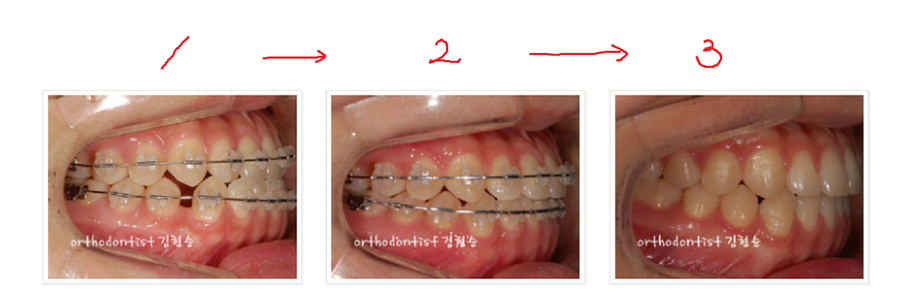

총 10개월 의 짧은 기간,

세라믹 교정을 진행하였습니다.

백문이 불여일견!

1, 2, 3 번의 순으로

주걱턱교정 진행과정과 개선사항을

사진으로 확인합니다.

사진들상의 1, 2, 3번

주걱턱교정 진행 사진들에서

확인가능하듯

- 아랫치아가 윗치아를 덮었던

반대교합(3급 부정교합)이

정상교합으로 개선 되었습니다.

- 윗치아가 아랫치아를

자연스럽게 덮는

정상교합으로 개선되어

음식 섭취시 종종

느끼던 턱관절이 뻐근하거나

턱관절에서 통증이 전해지던

턱관절 장애의 위험이

현저히 낮아졌습니다.

- 치열 개선으로

1번의 사진들 속에서 보이던

아랫 치아들 사이의 빈틈이

없어졌습니다.

4. 왼쪽으로 어긋나있던

치아중심선이 정중앙 으로

바로 잡혔습니다.

- 주걱턱으로 인해

길어보이던 턱이 작아보이고

돌출되었던 아랫턱이

들어가면서

얼굴이 작아보입니다.

6. 심미선을 살짝 벗어났던

아래입이 살짝 돌출된

돌출입이

심미선 안으로

들어가면서 개선

되었습니다.

7, 초승달, 접시 모양의

평면적이던 옆모습이

아랫턱선과 아랫입술선의 변화로

입체적인 옆모습으로 개선